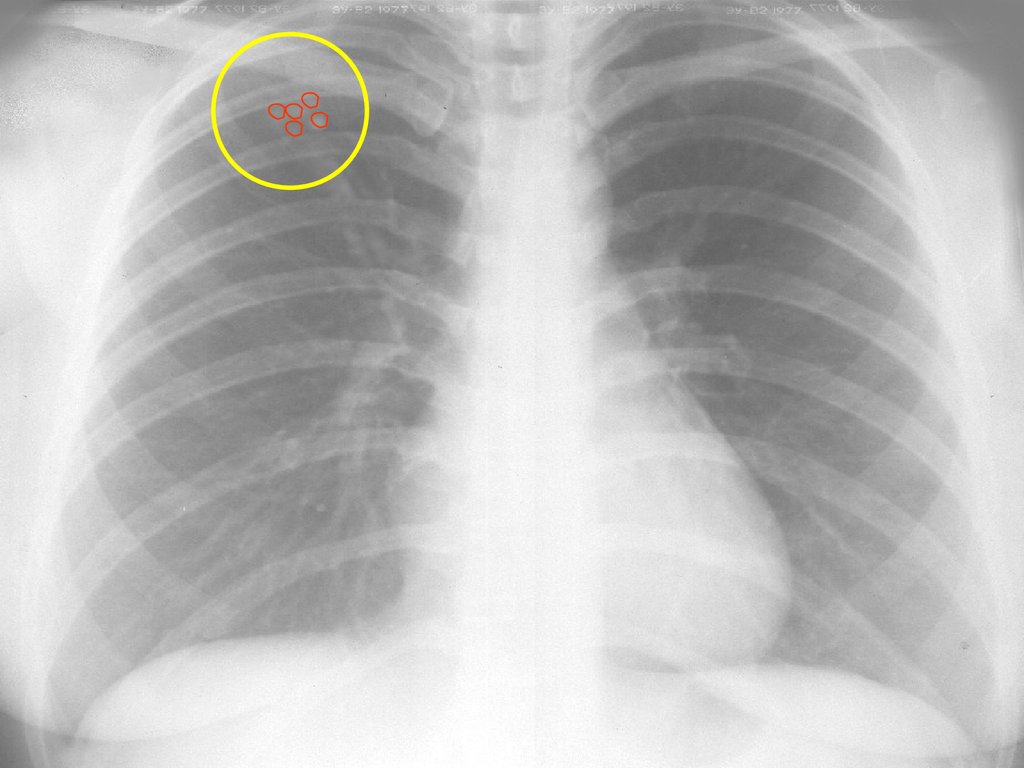

Рисунок 46-1. Это рентгенограмма грудной клетки 14-месячной девочки с 3-недельным кашлем в анамнезе, показывающая треугольную плотность в правой прикорневой области и тонкую воздушную ловушку (гиперлюцентность) в правой нижней доле.

Была проведена ригидная бронхоскопия с извлечением осколка стекла из правого главного бронха, что привело к исчезновению ее симптомов.